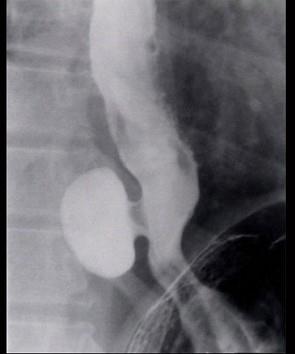

问题 女性患者,30岁,自觉胸骨后疼痛,时常嗝逆,可闻及恶臭,入院行X线钡餐检查,结果如图所示,应诊断为 ( )

选项 A、食管憩室 B、贲门癌 C、贲门失弛缓症 D、食管癌 E、食管平滑肌瘤

答案 A